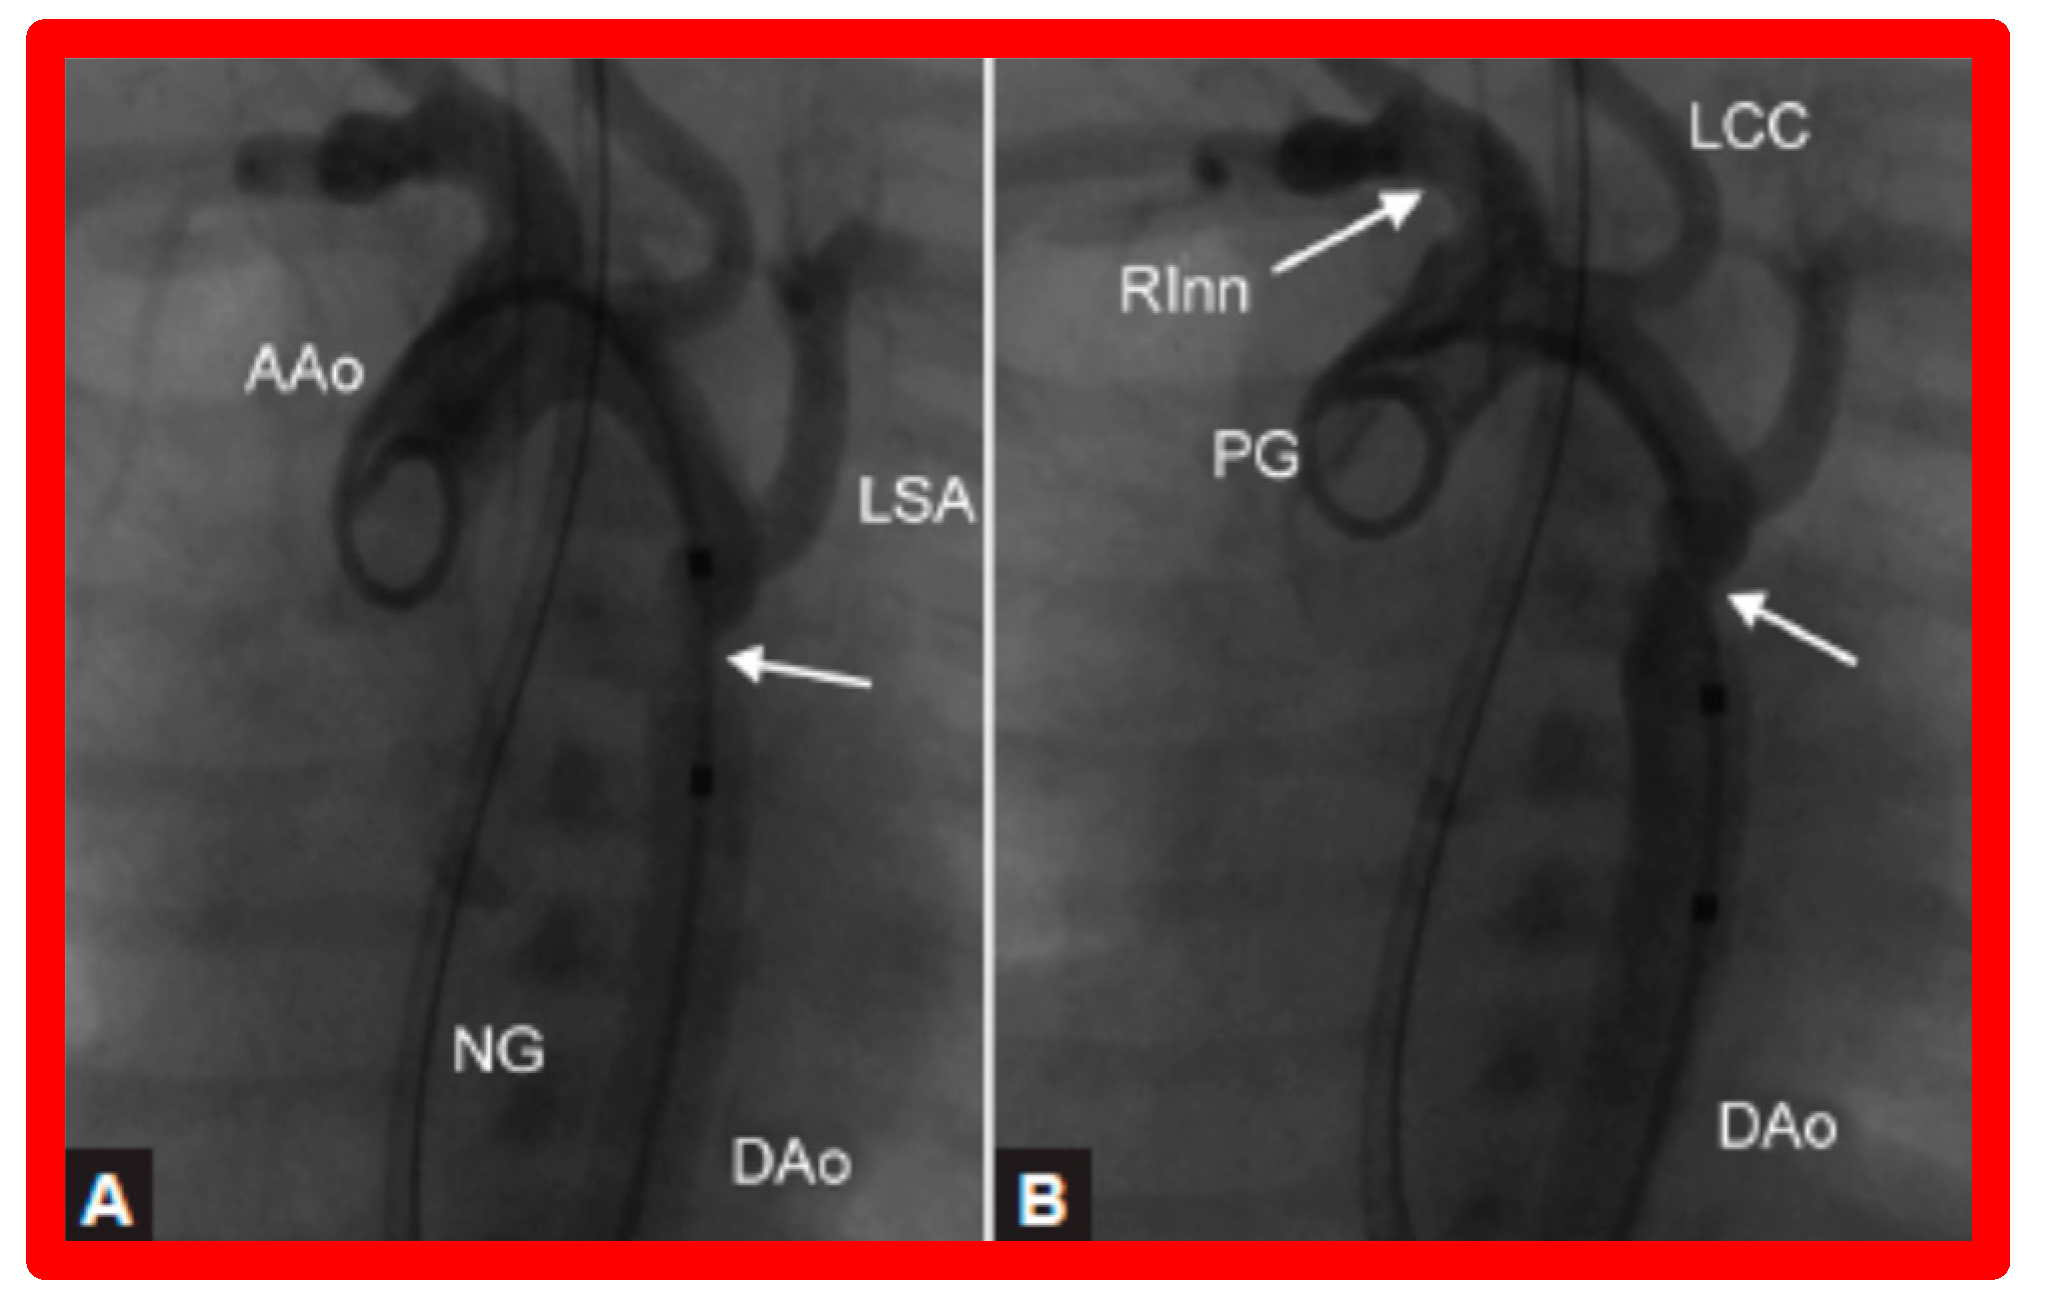

3.3. Aortic Coarctation, Native

3.4. Aortic Coarctation, Postsurgical